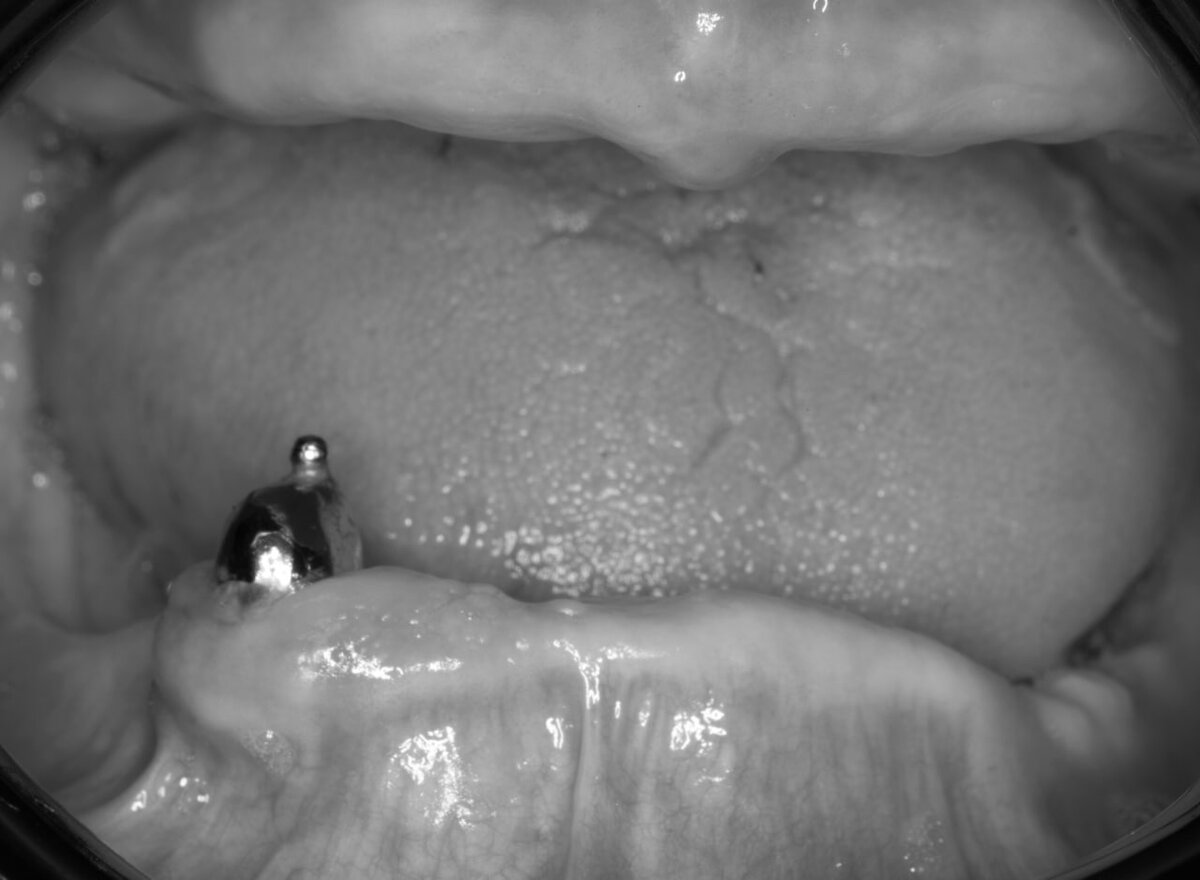

Обратилась пациентка с запросом на протезирование зубов. Во рту уже есть старые протезы — стоит вот такая конструкция. Мой ассистент сразу начал закидывать вопросами: "Что это? Зачем?"

Рассказываю: это перекрывающие протезы с использованием внутрикорневых аттачменов. В настоящее время используют, в основном, три системы внутрикорневых сферических аттачменов — это системы фирм RHEIN-83, BREDENT, SERVO DENTAL.

Основой этих систем является метод прецизионных аттачменов, фиксация которых происходит за счет сцепления сферической патрицы со штифтом, отливаемым из металла и укрепленном с помощью цемента в корне зуба, и эластичной матрицы, внутренняя поверхность которой соответствует негативной форме патрицы.